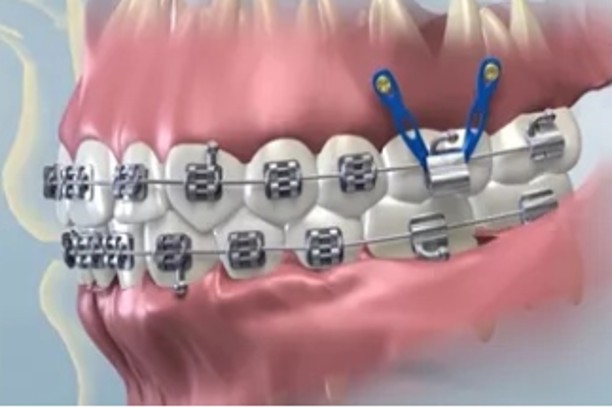

Mini implants (TADs)

Small anchors to support complex orthodontic movements.